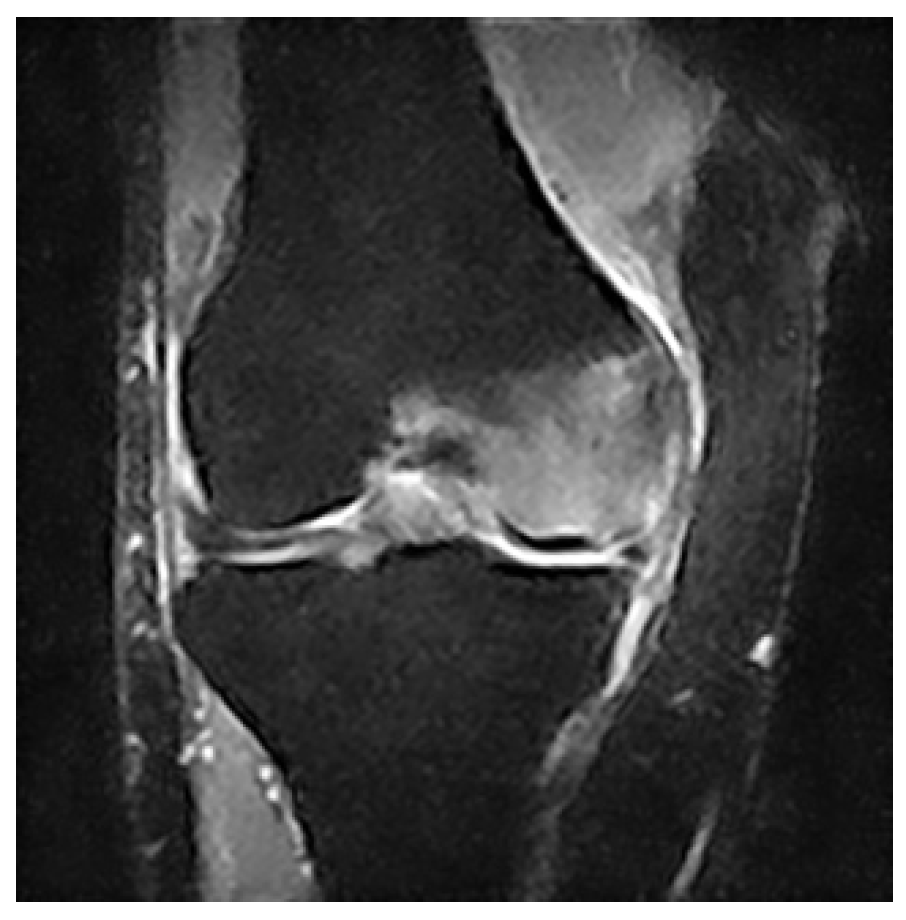

The archives of our institution were mined for the records of patients who had been diagnosed with primary BME of the knee from 1 January 2015 to 31 August 2021. The diagnosis was based on the sudden onset of acute non-traumatic knee pain and on abnormal bone marrow signal strength on MRI, specifically decreased bone marrow signal intensity on T1-weighted images and increased signal intensity on T2-weighted images, as presented in Figure 1.

Figure 1.

Coronal MRI image showing a typical BME pattern of our patients.